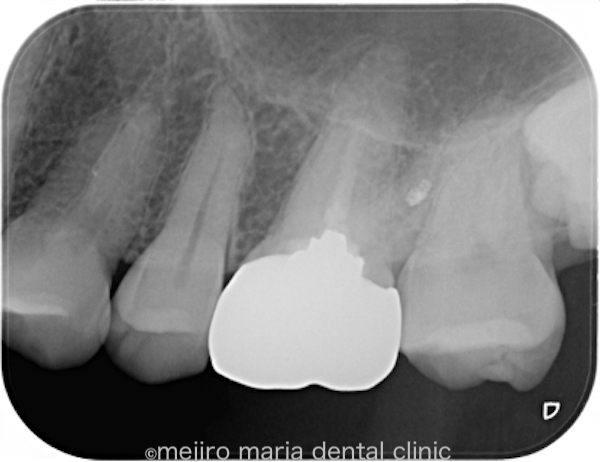

術前より根尖性歯周炎や症状がない症例に関しては90%以上の成功率となるため、ほぼ抜髄処置(初めて根管治療を行う場合)と同じくらいの成功率で治療を終了することができます。

今後は通常と同じように2年間の経過観察を行い、治療の経過を確認していく予定です。